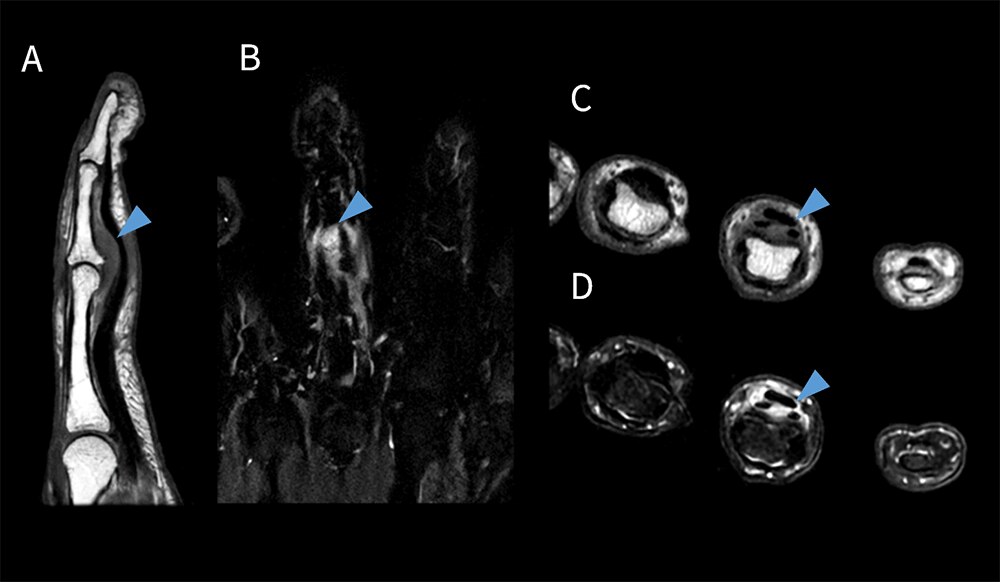

整形外科領域での臨床応用 ~高空間分解能と短時間撮像の両立~

整形外科領域の検査では、多くの撮像シーケンスや撮像断面が必要とされることが多く、加えて手指などの細かい構造物の描出も同時に求められるため、高分解能化に伴い撮像時間が延長することが懸念された。しかしながら、SIGNA™ Primeでは、面内の空間分解能やスライス分解能を向上させることによるノイズ増加が懸念される条件下でも、AIR™ Recon DLによってSNRが十分に担保され、同時に撮像時間の短縮まで可能となる。その結果、短時間かつ高分解能な画像が得られている(図8)。紹介検査においても、SIGNA™ Primeの導入により、以前までは依頼のなかった手指や腫瘍を対象とした検査依頼も増えており検査の幅が広がったと実感している。

図8 ガングリオン症例における手指撮像

A. T1強調像 Sagittal スライス厚:1.5mm 撮像時間:2:01 min

B. STIR像 Coronal スライス厚:2.0mm 撮像時間:1:50min

C. T1強調像 Axial スライス厚:2.0mm 撮像時間:1:47min

D. T2強調像 脂肪抑制 Axial スライス厚:2.0mm 撮像時間:1:40min